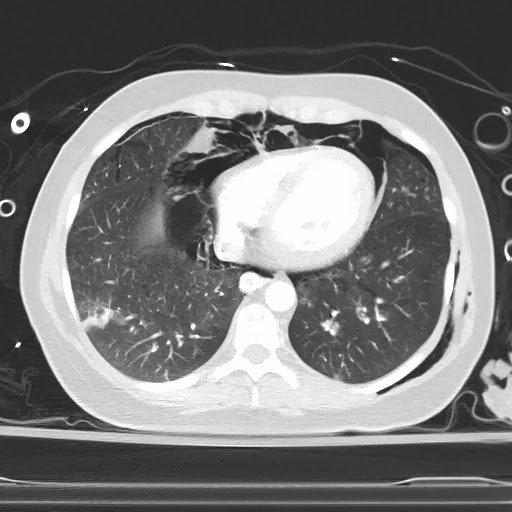

Although she was thought to probably have severe asthma, she underwent a CT pulmonary angiogram to rule out pulmonary embolism.  Here it is:

Air surrounds the heart (pneumopericardium and pneumothorax)